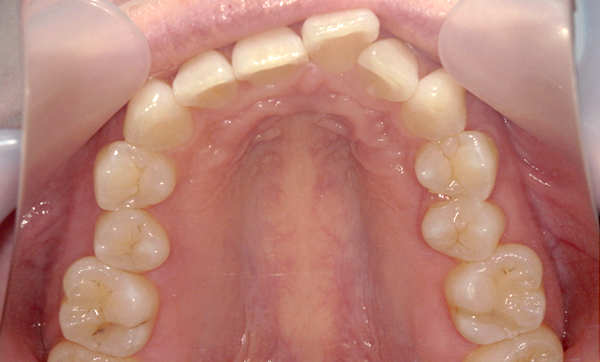

症例:上顎だけの部分矯正

症例_012 「出っ歯」症例

治療期間:8ヶ月金額:30万円+税20代女性出っ歯上の前歯だけ

| Before | After |

|---|---|